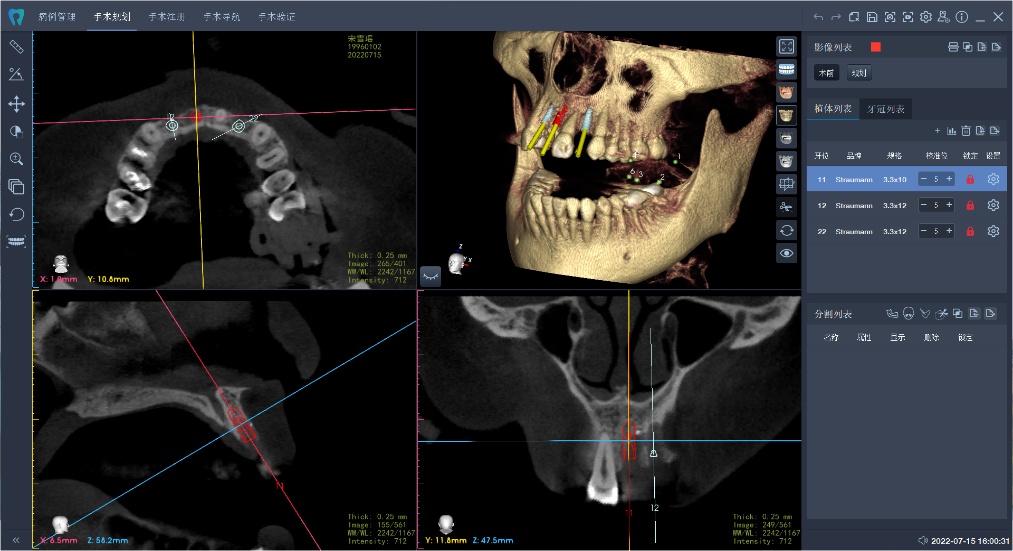

术前:可视化的体外模拟

术前,医生将患者的影像学资料导入机器人系统,进行种植体植入全过程的体外可视化模拟,这样手术团队能充分了解患者牙槽骨的骨量及解剖结构走向,更详尽地制订手术方案。